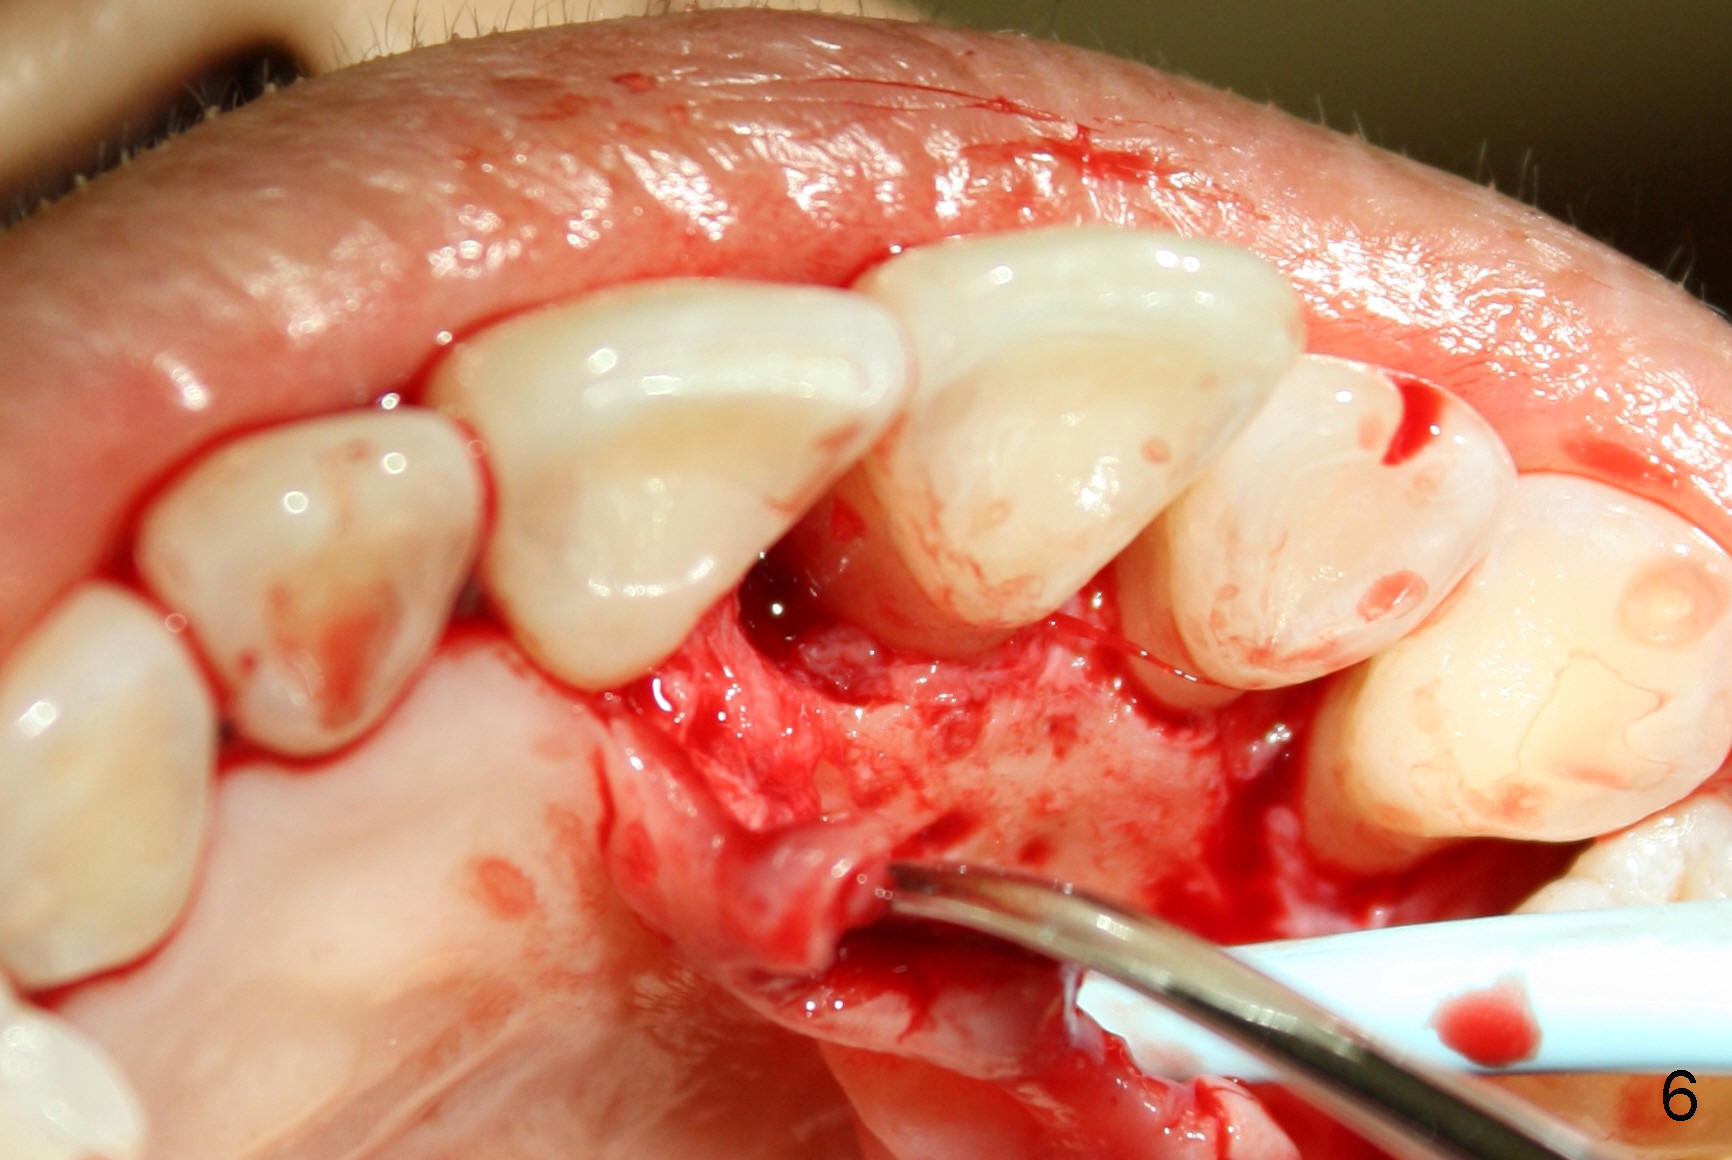

A 60-year-old lady had an abscess mesial to #9 six years ago (Fig.1,2 <), treated as a perio lesion by laser (Fig.3) and osseous surgery without bone graft (Fig.6, followed by CT exam revealing semi-circumferential bone loss (Fig.4,5). When the perio treatment failed, attention was paid to endo aspect (Fig.7-9). In fact the pulp was found to be vital when access to root canal therapy was made. As expected, the treatment failed again. The palatal fistula persisted. The infection was suspected to be a source of remote immediate implant site (#30). The tooth #9 was extracted. It appears that there is a semilunar crack line in the linguomesial root (Fig.12). When the socket healed 2 weeks post extraction (Fig.10), the #30 buccal defect was debrided with bone graft. There was no bone resorption 4 weeks post extraction (Fig.11); a 4.5x17 mm implant was placed (Fig.13-15). An immediate provisional was fabricated (Fig.16-18). Fig.19,20 were taken 3 months post implantation and 7 months post cementation, respectively. Dense bone forms around the implant coronally 4 years 5 months post cementation (Fig.21), while the gingiva is healthy palatally (Fig.22) and buccally (Fig.23).